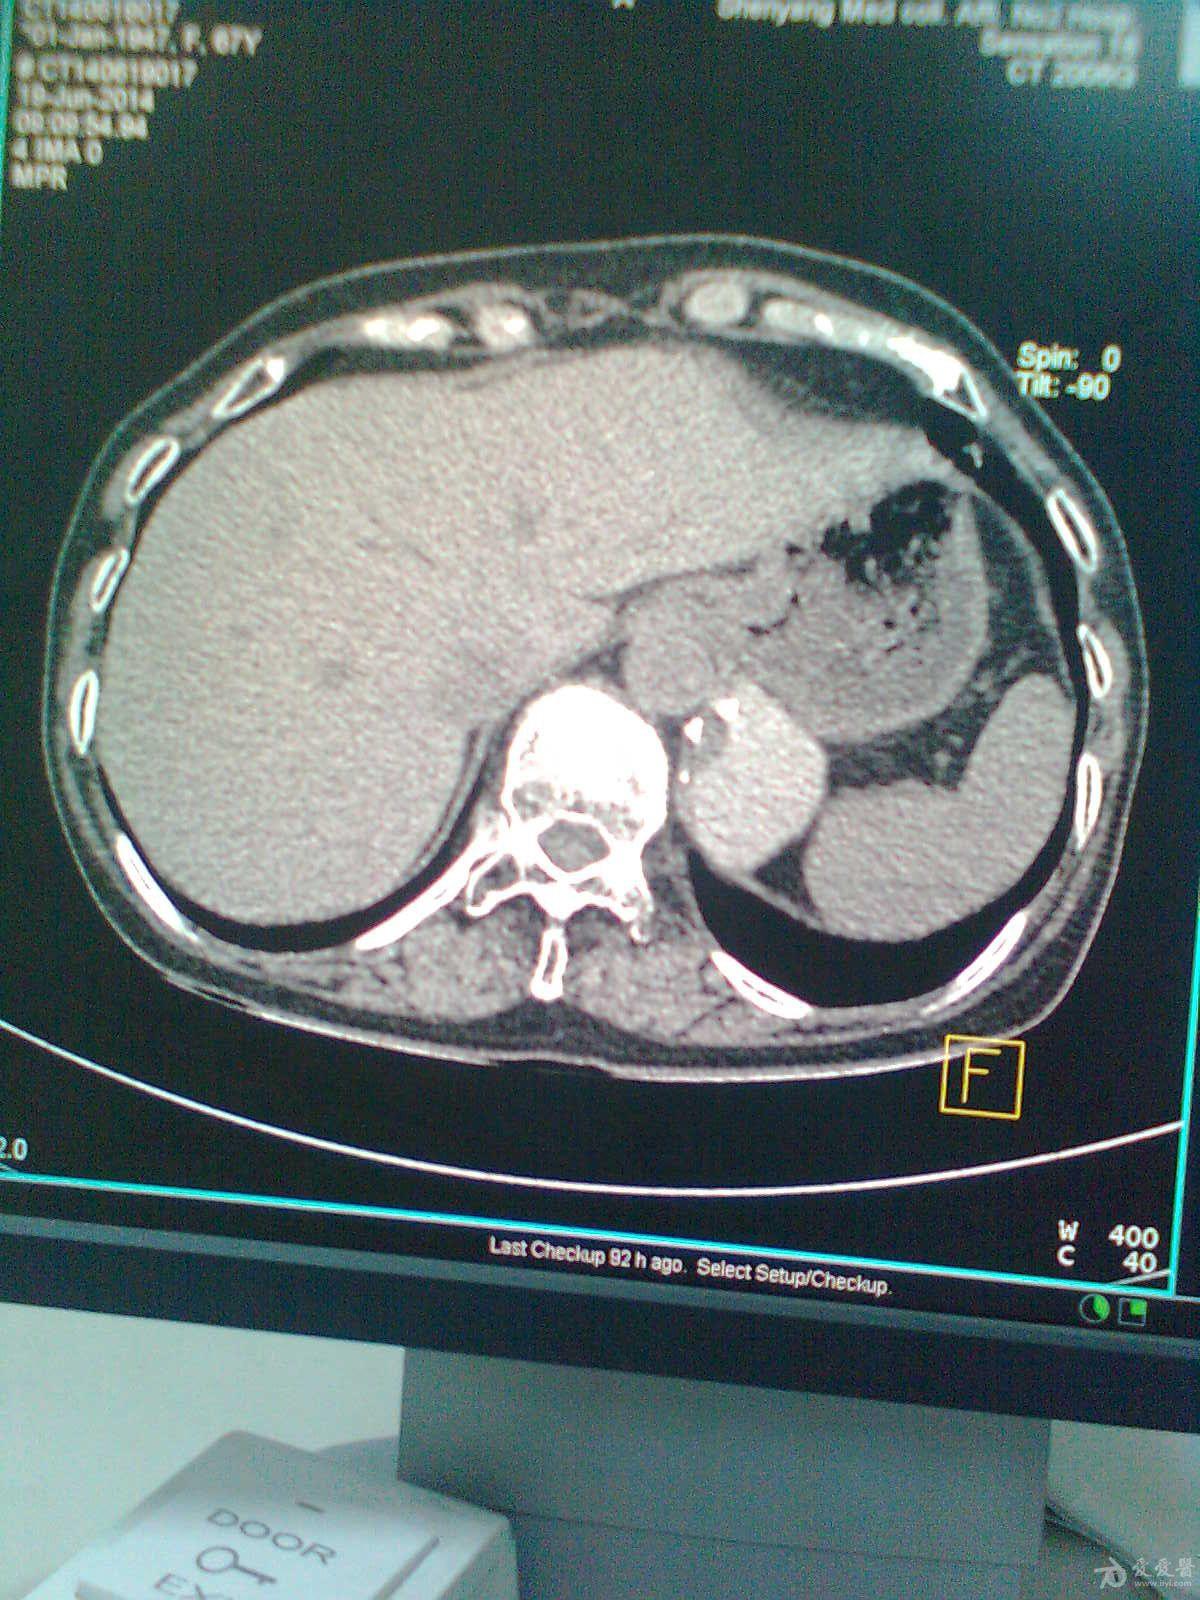

女性,29岁,查体发现左侧肾上腺区占位2天.

女,36岁,无任何症状,体检时超声发现左侧肾上腺区占位,ct扫描如图